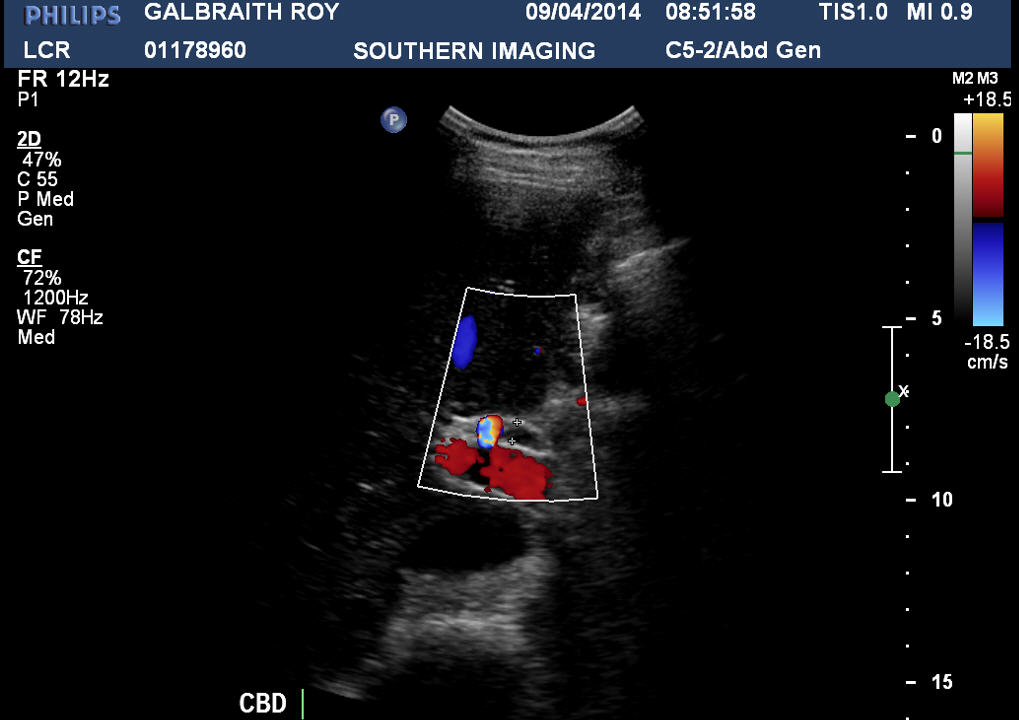

It was the end of March (31) when I had my CT Scan and on April the 1st I received the call – there is a lesion on your Kidney and I have booked you in for an Intravenous Ultra Sound in 2 days. Questions! Well I didn’t know what to say.. What did it mean? What was an intravenous ultra sound?

I really didn’t have to wait long, I was at my last Haematologist appointment where I was advised that I have “Key Characteristics” that warrant treatment for a malignant Kidney Cancer at the age of 37. My next appointment was in the care of Urology where it was again indicated that I have Kidney Cancer and treatment options were planned but nothing was conclusive during this time. Out of the blue in June’14 I received a phone call from my treating urologist and was advised that I would be booked in for a Biopsy, this rattled me emotionally as the plan had changed and I wasn’t convinced. You see my tumour is not in the kidney but it is on the Renal Artery – “not your classic kidney cancer” I was informed.

Biopsy Results – it has now been confirmed that I have Renal Chromophobe Carcinoma (a rare type of Kidney Cancer). The tumour is approx. 4cm in size sitting on the left renal artery and the plan is to remove the tumour, part of the artery and 1/3 of the kidney. Like all surgery it has its risks but mine has its own set of rules – I will be more than likely to be having open chest surgery as the location of the tumour is higher than normal and it is very close to the Aorta and right next to the spleen. There is also the possibility that a full removal of the left kidney may occur as the scans aren’t clearly showing if the tumour is touch both sides of the kidney. Surgery will occur on the 4/07/2014.In conclusion I guess I don’t meet the statistical guides of kidney cancer, never really had typical symptoms and due to a really thorough Haematologist I am lucky to have it diagnosed this early. I didn’t feel the need to google around on the web as I requested a Kidney Cancer pack which got sent out to me as well as the website both of which gave me plenty of information about Kidney Cancer and what to expect. I do however find myself a little isolated given the end diagnosis and very little information about this particular cell mutation and what are the statistics for this. I was never really overweight (obese), don’t drink alcohol (occasionally – 1 every 4 years), never smoked so I cant really see why I would have Kidney Cancer – but I do and what will be will be.